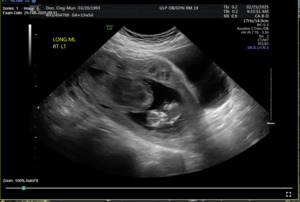

On admission for planned D&C, consents for laminaria placement, suction dilation and curettage under ultrasound guidance, possible uterine artery embolization, and possible hysterectomy were discussed and signed. The patient then underwent successful placement of a large and a medium-sized laminaria without complication. She subsequently underwent suction D&C with ultrasound guidance (Figure 3). Despite the prophylactic placement of 400 micrograms of rectal misoprostol and the administration of 20 units of Pitocin in IV fluids at the start of the case, the patient experienced significant hemorrhage during the procedure with an estimated blood loss of 1500 mL. Intraoperative findings raised concern for uterine rupture (Figure 4). A Foley balloon inflated with 30cc of saline was placed for attempted intrauterine tamponade (Figure 5), and a brisk blood loss of 500 mL immediately filled the foley catheter bag. Vaginal packing and intramuscular methergine were given as additional attempts to control the bleeding, but the patient’s hemodynamic status rapidly deteriorated. This necessitated volume resuscitation and transfusion of two units of packed red blood cells. An emergent exploratory laparotomy was then performed to identify the source of the bleeding with preparedness to repair any defects or perform a hysterectomy to prevent exsanguination. A thorough survey of the uterus, adnexa, and adjacent pelvic structures revealed no overt source of bleeding, uterine rupture, or organ invasion. The uterine and bladder serosa were intact. No hemoperitoneum was found. Further inspection revealed no additional blood loss beyond the 500 mL noted in the foley bag. Blood loss was ppropriately corrected for, and the patient became hemodynamically stable. The abdomen was closed, and the patient was transferred to interventional radiology for uterine artery embolization, prevented additional bloodloss. Following embolization, the patient was noted to be stable and extubated without issue.